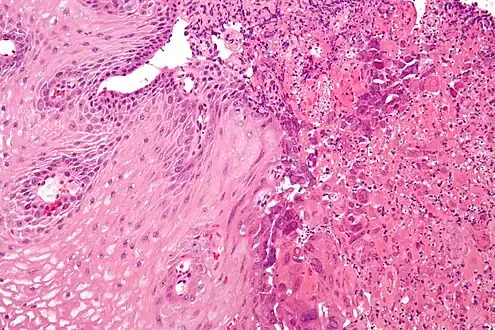

Upper Endoscopy often reveals ulcers throughout the esophagus with intervening normal-appearing mucosa. In severe cases the ulcers can coalesce and on rare occasions have a black appearance known as black esophagus.[8] While the diagnosis of herpes esophagitis can be inferred clinically it can only be accurately diagnosed through endoscopically obtained biopsies with microscopic evaluation by a pathologist finding the appropriate inclusion bodies and diagnostic immunochemical staining.[9] False negative findings may occur if biopsies are taken from the ulcer rather than from the margin of the ulcer as the inclusion particles are to be found in viable epithelial cells. Viral tissue culture represents the most accurate means of diagnosing the precise cause.